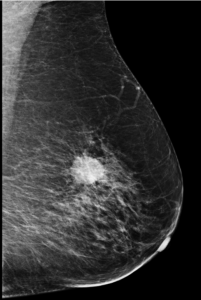

Caso 22

Explicación: Al tener 85 años, la mama tendrá un patrón graso y la lesión se verá fácilmente. Se hacen ambas proyecciones para tener una visión completa de la mama.